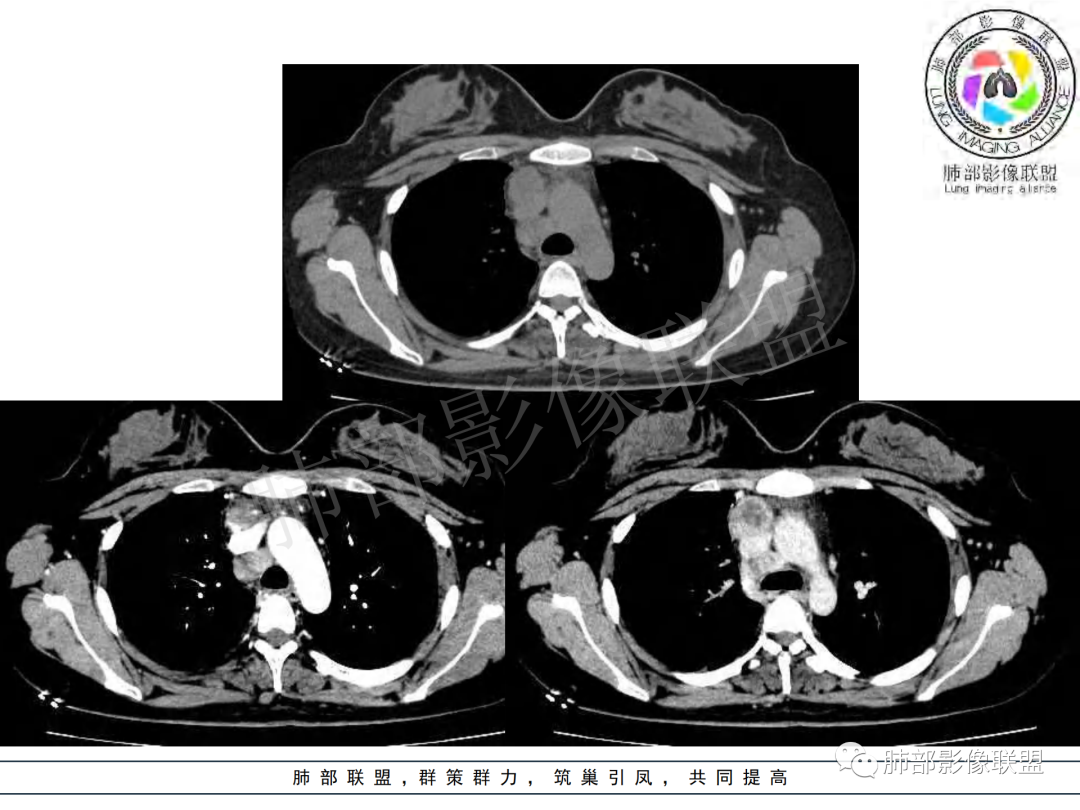

纵隔多组及右侧肺门多发肿大淋巴结,部分融合,不均匀强化,内见斑片状坏死区及环状强化,后者坏死边界尚清晰,肺门区肿大淋巴结与肺组织边界不清,年轻女性,8个月病史,发热首发症状,考虑淋巴结核并向肺内侵及(破溃?),鉴别淋巴瘤

女,20,病程长达8月,发热、胸痛、右侧胸腔积液病史。胸部CT:右肺门旁不规则肿块影,右中间支气管腔内结节,纵隔多发淋巴结肿大;强化不均匀,灶性坏死灶,环形强化;右侧少量胸腔积液并局部肉芽肿样突起。年轻女性,长病程,多部位,考虑慢性炎症,结核?鉴别肿瘤。

年轻女性,慢性病程,发热、胸痛。右肺门旁不规则肿块影,纵隔多发淋巴结肿大;强化不均匀,环形强化;右侧少量胸腔积液;首先考虑结核,鉴别肿瘤,结节病。

慢性病程,前纵隔右肺门旁多发淋巴结肿大;强化不均匀,环形强化;右侧少量胸腔积液;考虑结核,鉴别结节病。

青年女性,发热、胸痛、右侧胸腔积液病史,病程8个月。曾多次抗炎后均有好转。CT:右肺门旁肿块影,双侧胸膜结节,纵隔多发淋巴结肿大,边缘模糊;增强渐进性明显强化,纵膈淋巴结较彻底坏死灶,边缘环形强化。考虑结核,鉴别恶性肿瘤。

女性,20岁。高热、畏寒。右肺上叶近肺门区不规则肿块,周围斑点、片小结节影伴肿大淋巴结,肿块包绕并突入右主支气管腔内,增强后肿块不均匀强化,淋巴结环形强化中心低密度,考虑结核。

本例患者,年轻女性,慢性病程,多次抗感染治疗效果不佳,实验室检查示白细胞及中性粒细胞不高,不支持普通细菌感染,虽然肺泡灌洗液X-Pert检测阴性,结合患者胸部CT结核感染亦不能排除,胸部CT主要表现为右侧肺门及纵隔淋巴结肿大,仔细观察不难发现右中间支气管内新生物凸向管腔内,增强扫描,右肺门(10R)及纵隔淋巴结(2R,4R)明显不均匀强化,内部呈不规则低密度无强化区,被周边高强化区包绕(环形强化)的特点,首先应当想到纵隔淋巴结结核诊断。淋巴结分布亦不符合肺部恶性肿瘤迁徙途径。